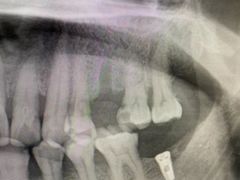

• 牙博士口腔品牌连锁(杨浦店)

• -牙博士口腔品牌连锁(杨浦店)